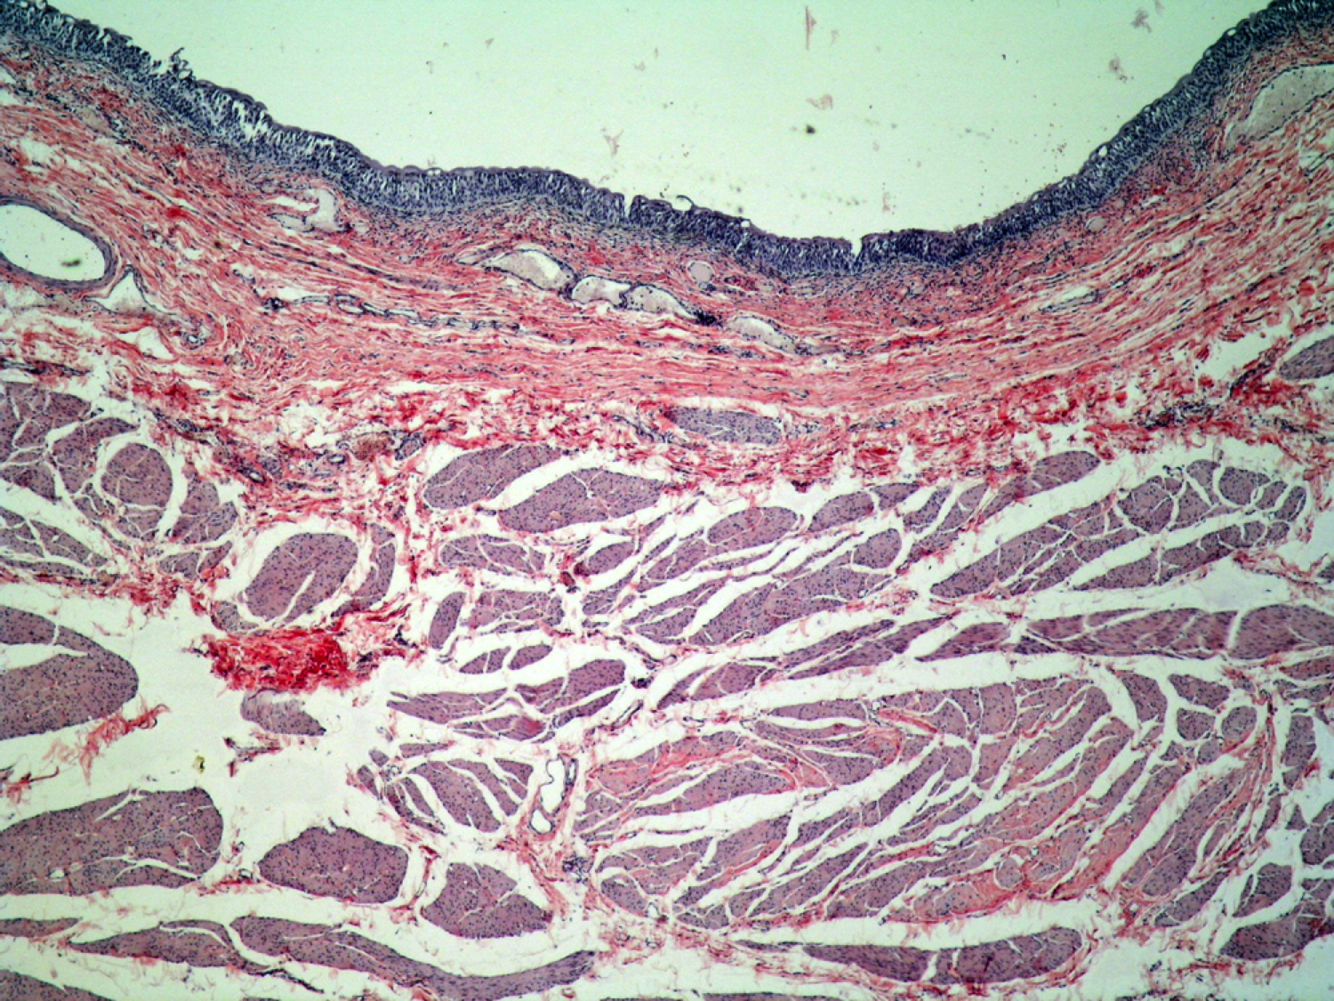

Identify

Transitional Epithelium from Human Bladder (relaxed)

H & Chromotrope staining

Epithelium just the dark purple later at top